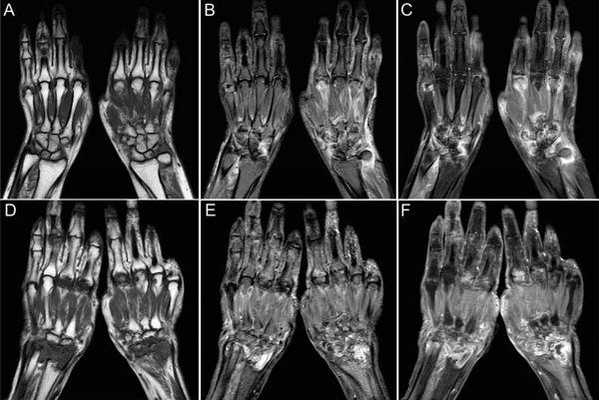

(Слева) На заднепередней рентгенограмме визуализируются нормальные сесамовидные кости, расположенные у 1-го и 2-го пястно-фалангового суставов и 1 -го межфалангового сустава. Размер может быть разным. Сесамовидные кости у 1-го пястно-фалангового сустава кисти наблюдается практически постоянно.

(Справа) На заднепередней рентгенограмме визуализируется нормальная сесамовидная кость у 5-го пястно-фалангового сустава. Эта очень маленькая кость может оказаться очень плотной, учитывая ее размер. Костномозговые полости и кортикальные края лучше определяются у более крупных сесамовидных костей. (Слева) На осевой КТ 1-го пястно-фалангового сустава визуализируются сглаженные, покрытые кортикальным слоем сесамовидные кости с фасеточным контуром, обращенным к головке пястной кости. Обратите внимание, что сесамовидные кости исходят из капсулы пястно-фалангового сустава, а не располагаются в прилежащем сухожилии длинного сгибателя большого пальца.

(Справа) Осевая МРТ Т2ВИ у другого пациента: обращает на себя внимание взаимоотношение сухожилия длинного сгибателя большого пальца с 1 -м пястно-фаланговым суставом и прилежащими отдельными фасеточными сесамовидными костями Я, заключенными в капсулу 1 -го пястно-фалангового сустава. (Слева) На заднепередней рентгенограмме визуализируется выступающая парамногоугольная кость, расположенная непосредственно латерально от 1-го пястно-фалангового сустава. Медиальнее визуализируется меньшая, несколько более плотная центральная кость запястья около дистального ладьевидного сустава с трапециевидной костью.